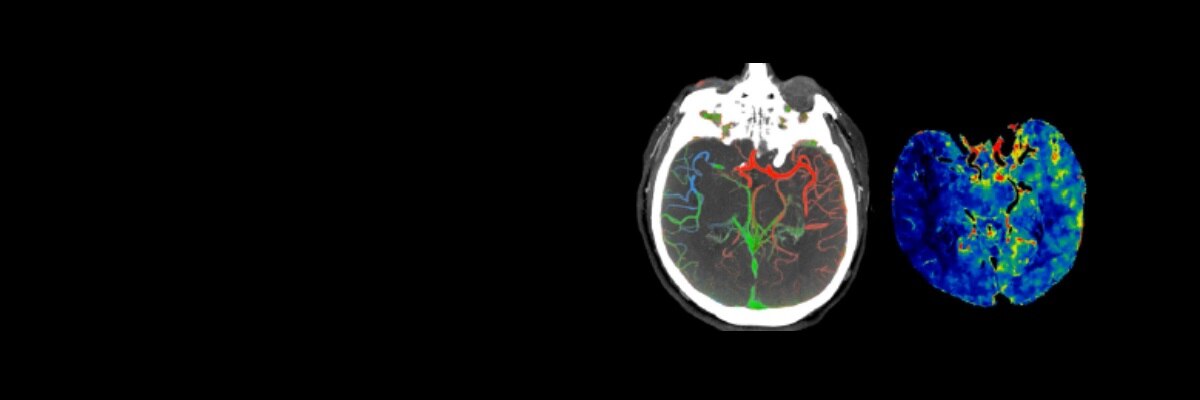

Parcours patient